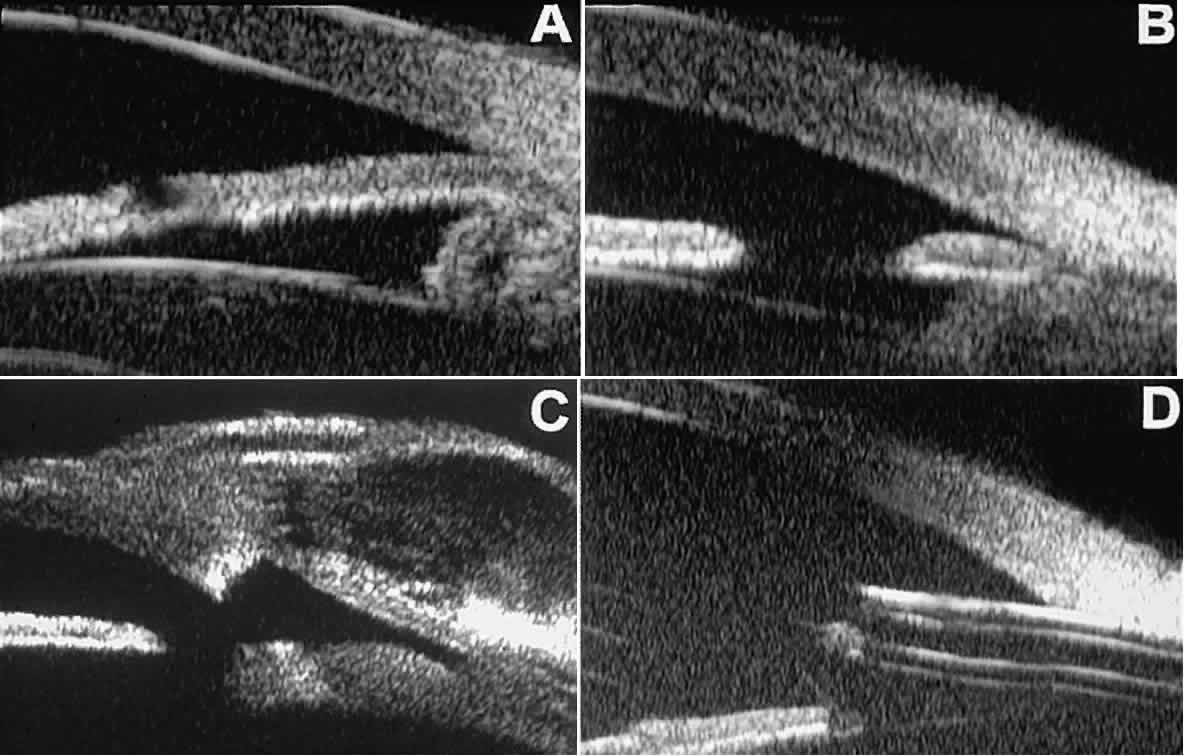

Postoperative UBM imaging of the anatomic changes caused by glaucoma surgery often helps to explain mechanisms of success and failure of the various surgical procedures (Fig. 12).3,4 After laser iridotomy, UBM can show whether the iridotomy is partial thickness (see Fig. 12A) or full thickness (see Fig. 12B) and whether the plane of curvature of the peripheral iris has changed compared with the pretreatment findings. After trabeculectomy (see Fig. 12C), UBM can show whether the scleral aperture is patent or blocked internally, whether the peripheral iridectomy is open or blocked, and whether the filtering bleb is flat, shallow, or deep.9 After tube shunt surgery (see Fig. 12D), UBM can show the position of the tip of the tube and whether its orifice is open or plugged.

Fig. 12. UBM features in glaucomatous eyes after treatment or filtering surgery. A. Incomplete peripheral iridectomy created by laser. B. Full-thickness peripheral iridectomy created by laser. C. Postoperative features of trabeculectomy including peripheral iridectomy, inner scleral defect, thin residual scleral flap, and overlying conjunctival filtering bleb. D. Tube shunt projecting radially into anterior chamber; note that the tube “shadows” deeper structures.